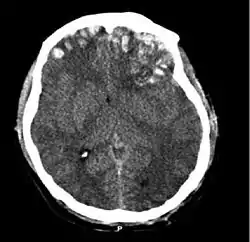

وتشمل الأسباب السقوط، واصطدام المركبات، والعنف. تحدث الصدمة الدماغية نتيجة للتسارع أو التباطؤ المفاجئ داخل الجمجمة أو عن طريق مزيج معقد من كل من الحركة والتأثير المفاجئ. وبالإضافة إلى الأضرار الناتجة في لحظة الإصابة، قد تؤدي مجموعة مختلفة من الأحداث في الدقائق والأيام التالية للإصابة إلى إصابة ثانوية. وتشمل هذه العمليات تغييرات في تدفق الدم في الدماغ والضغط داخل الجمجمة. وتشمل بعض تقنيات التصوير المستخدمة للتشخيص التصوير المقطعي والتصوير بالرنين المغناطيسي.

الاختبار الإشعاعي المفضل في حالة الطوارئ هو التصوير المقطعي المحوسب (CT)؛ فهو سريع، ودقيق، ومتاح على نطاق واسع.[69] ويمكن إجراء عمليات المسح المقطعي في وقت لاحق لتحديد ما إذا كانت الإصابة قد تطورت.[2]

يمكن للتصوير بالرنين المغناطيسي أن يُظهر المزيد من التفاصيل عن التصوير المقطعي، كما يمكنه إضافة معلومات عن النتيجة المتوقعة على المدى الطويل.[15] وهو أكثر فائدة من التصوير المقطعي للكشف عن خصائص الإصابة مثل إصابة المحور العصبي المنتشرة في المدى الطويل.[2] ومع ذلك، لا يستخدم التصوير بالرنين المغنطيسي في حالات الطوارئ لعدة أسباب منها عدم فعاليته النسبية في الكشف عن النزف والكسور، واكتسابه الطويل للصور، وعدم إمكانية وصول المريض للجهاز، وعدم توافقه مع العناصر المعدنية المستخدمة في الرعاية في حالات الطوارئ.[15] وهناك بديل للتصوير بالرنين المغناطيسي منذ عام 2012 هو تتبع الألياف عالية الوضوح (HDFT).[70]

وتشمل اضطرابات الحركة التي قد تتطور بعد الإصابة الدماغية الرضية: الرعاش، والرنح (حركات العضلات غير المنسقة)، والرمع العضلي (تقلصات تشبه الصدمة في العضلات)، وفقدان نطاق الحركة والسيطرة.[84] ويزداد خطر الصرع التالي للرض مع شدة الرضة (الصورة في اليسار) ويزداد بشكل خاص مع أنواع معينة من صدمات الدماغ مثل الكدمات الدماغية أو الورم الدموي.[107] الأشخاص الذين يعانون من التشنجات المبكرة، تلك التي تحدث في غضون أسبوع من الإصابة، لديهم خطر متزايد من الصرع التالي للرضة (النوبات المتكررة التي تحدث بعد أكثر من أسبوع من الصدمة الأولية).[116] كما قد يفقد أو يعاني المصابون من تغير البصر أو السمع أو الشم.[3]